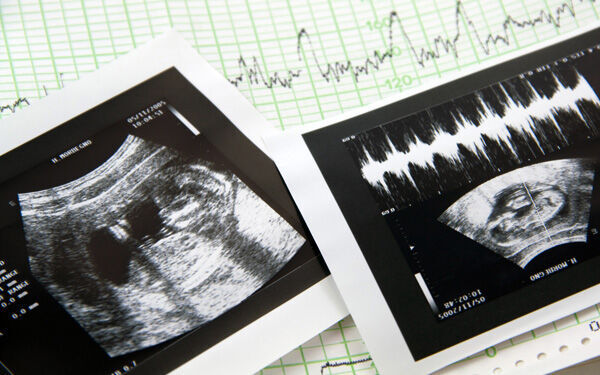

© wlablack - Fotolia.com

顔だけだった産毛が全身に

全身に産毛(胎毛)が生えてきて、赤ちゃんを羊水の刺激から守り、体温を一定に保ってくれます。頭髪が生えはじめるのもこの頃です。17週の赤ちゃんの身長は約18cm、体重は150g程度。19週の赤ちゃんの身長は約25cm、体重は250g程度。妊婦さんの子宮底長(恥骨の結合部から子宮の上まで)は約15cm。

皮膚が赤色になってくる

脂肪が増えてくるので、不透明な赤い肌になってきます。

胎内で活発に動く

筋肉がついて、さらに活発に動くように。おなかの中でグルグルと回るように動きます。

感覚や内臓のはたらきもどんどん発達してくる

指しゃぶりをはじめる

五感の中でも最初に発達し、5ヶ月でほぼ完成しているのが触覚です。この頃は口に触れる指を確かめるように、指しゃぶりをしています。これは生まれた後、おっぱいを吸う練習をしているのだという説もあります。

内臓のはたらきが発達する

内臓のはたらきも、徐々に発達してきます。腎臓と膀胱はほとんど完成しているのでおしっこをしていますし、肝臓では血液を作りはじめます。